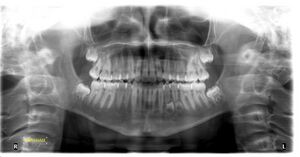

إعادة توليد الأسنان أو إعادة تجديد الأسنان (Tooth regeneration)، هي إحدى إجراءات الطب التجديدي قائمة على الخلايا الجذعية في مجال هندسة الأنسجة وعلم أحياء الخلايا الجذعية، يهدف إلى تعويض الأسنان التالفة أو المفقودة عن طريق إعادة نموها من الخلايا الجذعية ذاتية الاغتراس.[1]

تُستخدم الخلايا الجذعية الجسدية كمصدر للأسنان الجديدة المُهندسة حيوياً، حيث يتم جمعها وإعادة برمجتها إلى خلايا جذعية محرضة متعددة القدرات، والتي يمكن وضعها مباشرة في الصفيحة السنية أو وضعها في پوليمر حيوي قابل للامتصاص[2] على شكل السن الجديد.[3]